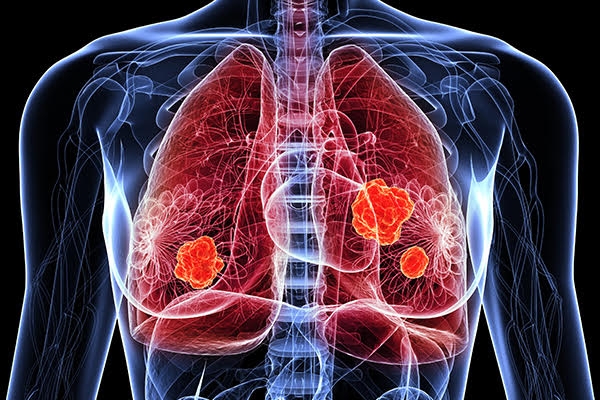

폐암은 원발성 폐암을 말하며 원발성 폐암은 폐에서 기원하는 악성 종양을 말한다. 폐로 전이된 암은 폐로 전이된 것으로 분류되며, 폐암이라기 보다는 기원 장기로 전이된 것으로 분류된다. 폐암은 조직학적 유형에 따라 크게 소세포폐암과 비소세포폐암으로 분류된다.

이 분류의 이유는 소세포 폐암이 치료 및 예후 측면에서 다른 유형의 폐암과 확연히 다른 특징을 가지고 있기 때문입니다.